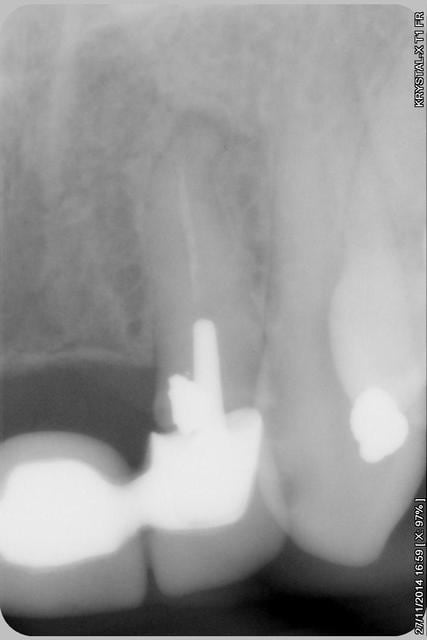

la suite

reconstitution, taille pour empreinte et provisoire (pas beau mais il sera remplacé)

Img 2181 yijzhz - Eugenol

Img 2182 lhh6e0 - Eugenol

015xcopier lyppuy - Eugenol

Img 2183 pmo5my - Eugenol

016copier zr2pom - Eugenol

Img 2176 y7mrkt - Eugenol